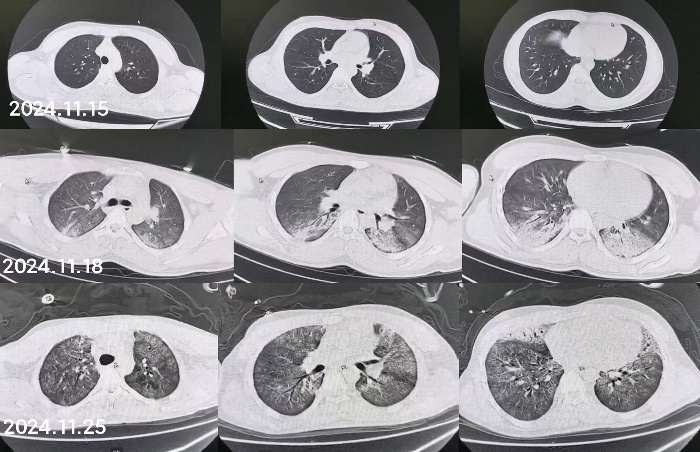

1 病例资料2024-11-15,某工地操作间有值班人员3人,分别为上铺(距地面1.8 m)A某,下铺(距地面0.4 m)B某、C某,事发当天为午休时间,设备出现故障,下午14时维修人员D某进入操作间维修,并将门窗打开,完成维修操作;事发后24 h内4名患者均出现不同程度的恶心、呕吐等消化道症状,起初考虑可能与食物中毒有关,前往当地医院就诊,完善血便常规、胸腹CT等相关检查未见明显异常,在医院给予吸氧补液静卧留观,留观期间4人先后出现不同程度的咽痛、咳嗽、胸闷、憋气等不适,吸氧不能缓解,再次行胸部CT检查示双肺弥漫性改变,间质改变可能,考虑为吸入有毒有害气体,后经采样检测操作间气体残留为全氟-4-甲基-2戊稀[Perfluoro(4-methylpent-2-ene),D1](D1纯度99.92%),导致急性呼吸窘迫综合症(acute respiratory distress syndrome, ARDS)。参照2002年职业性急性有机氟中毒诊断标准[1],A某诊断为急性中度有机氟气体中毒,B某、C某、D某诊断为急性重度有机氟气体中毒(PaO2/FiO2 < 100 mmHg,1 mmHg=0.098 kPa)。立即给予大剂量(120 mg)甲泼尼龙琥珀酸钠治疗,同时补充多种微量元素,加用甲钴胺、硫辛酸,钙剂解毒,后续加用特殊解毒剂乙酰胺治疗。治疗1周后,上铺的A某胸闷、憋气症状较前好转,影像未见明显进展,但患者仍遗留有间断气短症状;其余人员病情持续恶化,出现呼吸衰竭,转入重症医学科,给予气管插管接呼吸机辅助通气,维修人员D某上呼吸机后能基本维持,但不能脱机,继续观察患者病情变化;而下铺患者B某、C某症状不断加重,即使给予呼吸机治疗低氧状态仍未见明显改善,于2024-11-29转入本院进一步治疗。B某、C某入本院时查体:双肺叩诊呈清音,双肺呼吸音粗,可闻及干湿性啰音,具体指标见表 1,图 1、2为肺部影像进展情况。入院给予镇静镇痛、机械通气及抗感染、抗炎、抑酸等治疗,呼吸困难仍持续加重,存在难以纠正的低氧血症及高碳酸血症,表现为ARDS,有体外膜肺氧合(extracorporeal membrane oxygenation, ECMO)治疗指征,参考国内外相关救治经验[2-6],给予患者静脉-静脉ECMO(veno-venous extracorporeal membrane oxygenation, V-V ECMO)治疗,具体参数见表 2。

| 图 2 C某发病第1、3、10天胸部CT |

同时给予镇痛、镇静联合肌松,去甲肾上腺素泵入维持血压,俯卧位通气,B某入院后出现高热,经验性给予美罗培南联合万古霉素抗感染治疗,后降阶梯调整为哌拉西林他唑巴坦联合万古霉素治疗;C某抗感染方案为经验性使用万古霉素联合哌拉西林他唑巴坦治疗,痰培养出鲍曼不动杆菌后改为替加环素、头孢哌酮舒巴坦及万古霉素治疗;根据《刺激性气体中毒诊治专家共识》[5]中关于重症患者的治疗措施,同时给予2人泮托拉唑抑酸护胃,氨溴索、富露施化痰、甲泼尼龙抗炎、西维来司他纳及乌司他丁清除炎性介质,维生素C抗氧化、保肝、输血补液,纤支镜吸痰及肺泡灌洗,维持水电解质平衡及营养支持治疗,特别考虑到肺损伤情况,在使用有创通气时给予超保护性通气策略[5, 7];2人仍先后出现气胸、纵膈气肿,行胸腔闭式引流;持续V-V ECMO治疗15 d后,肺部纤维化不可逆转,高分辨率CT肺纤维化评分 > 75%(图 3、4),符合终末期肺病标准,有肺移植指征[8],经评估后2人顺利完成病变肺组织切除(图 5),双侧序贯肺移植,术后患者复查胸片肺部恢复正常(图 6),2位患者术后气管切管接呼吸机辅助通气,并给予泼尼松、他克莫司、吗替麦考酚酯抗排异治疗,其余根据病情给予万古霉素调节肠道菌群、抗感染、保肝、抗凝、呼吸康复锻炼等治疗,后顺利脱机、拔除气切套管,病情稳定出院,后续规律复查胸部CT(图 7)恢复良好。